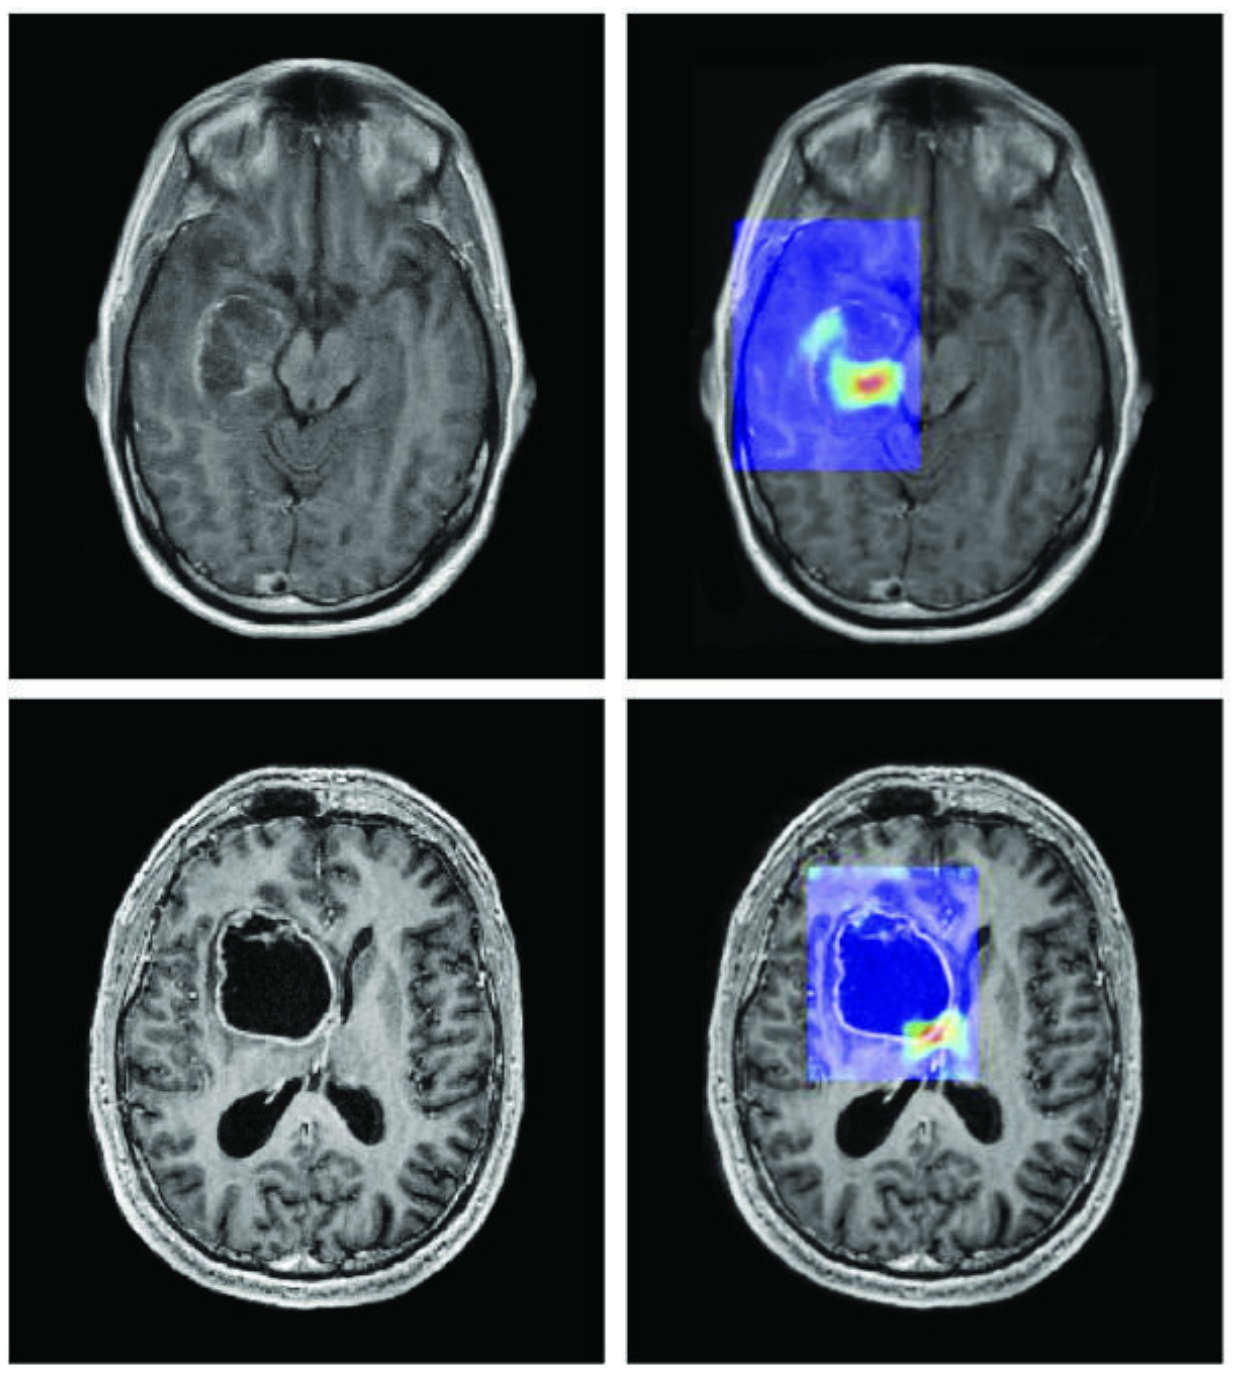

Imatge extreta de: CA Cancer J Clin març/abril 2019. DOI: 10.3322/caac.21552. Llicència: CC BY 4.0.

Tres situacions concretes il·lustren ja aquesta coexistència eficaç entre l’humà i la IA. En medicina, sistemes d’IA analitzen milers de radiografies en qüestió de segons per detectar signes precoços de càncer [1]; però és el metge qui interpreta el context clínic del pacient, estableix el diàleg amb ell i decideix el protocol de tractament adequat: la IA accelera el diagnòstic, però és l’humà qui n’assumeix la responsabilitat i el sentit. A la indústria, els fabricants d’automòbils utilitzen la IA per controlar la qualitat a les línies de producció [2], identificant defectes invisibles a ull nu; però són els enginyers els que dissenyen els processos, ajusten els llindars de tolerància i prenen decisions quan un problema surt del marc previst per l’algoritme. Finalment, en la recerca científica, la IA desenvolupada per DeepMind ha permès predir l’estructura tridimensional de més de dos-cents milions de proteïnes [3], una feina que hauria trigat segles si els investigadors haguessin treballat sols; però són els biòlegs i els químics els que formulen les hipòtesis, dissenyen els experiments i transformen aquestes prediccions en tractaments o materials nous. En cadascun d’aquests casos, la lliçó és la mateixa: la IA no substitueix l’humà, sinó que multiplica la seva capacitat d’acció.